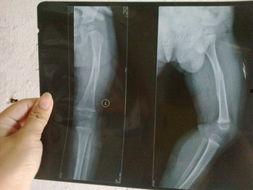

在正式开始打石膏之前,医生会先对你进行一系列的检查,确保骨折的情况已经稳定。这个过程可能包括X光片、CT扫描等,以便医生能够清楚地了解骨折的具体情况。